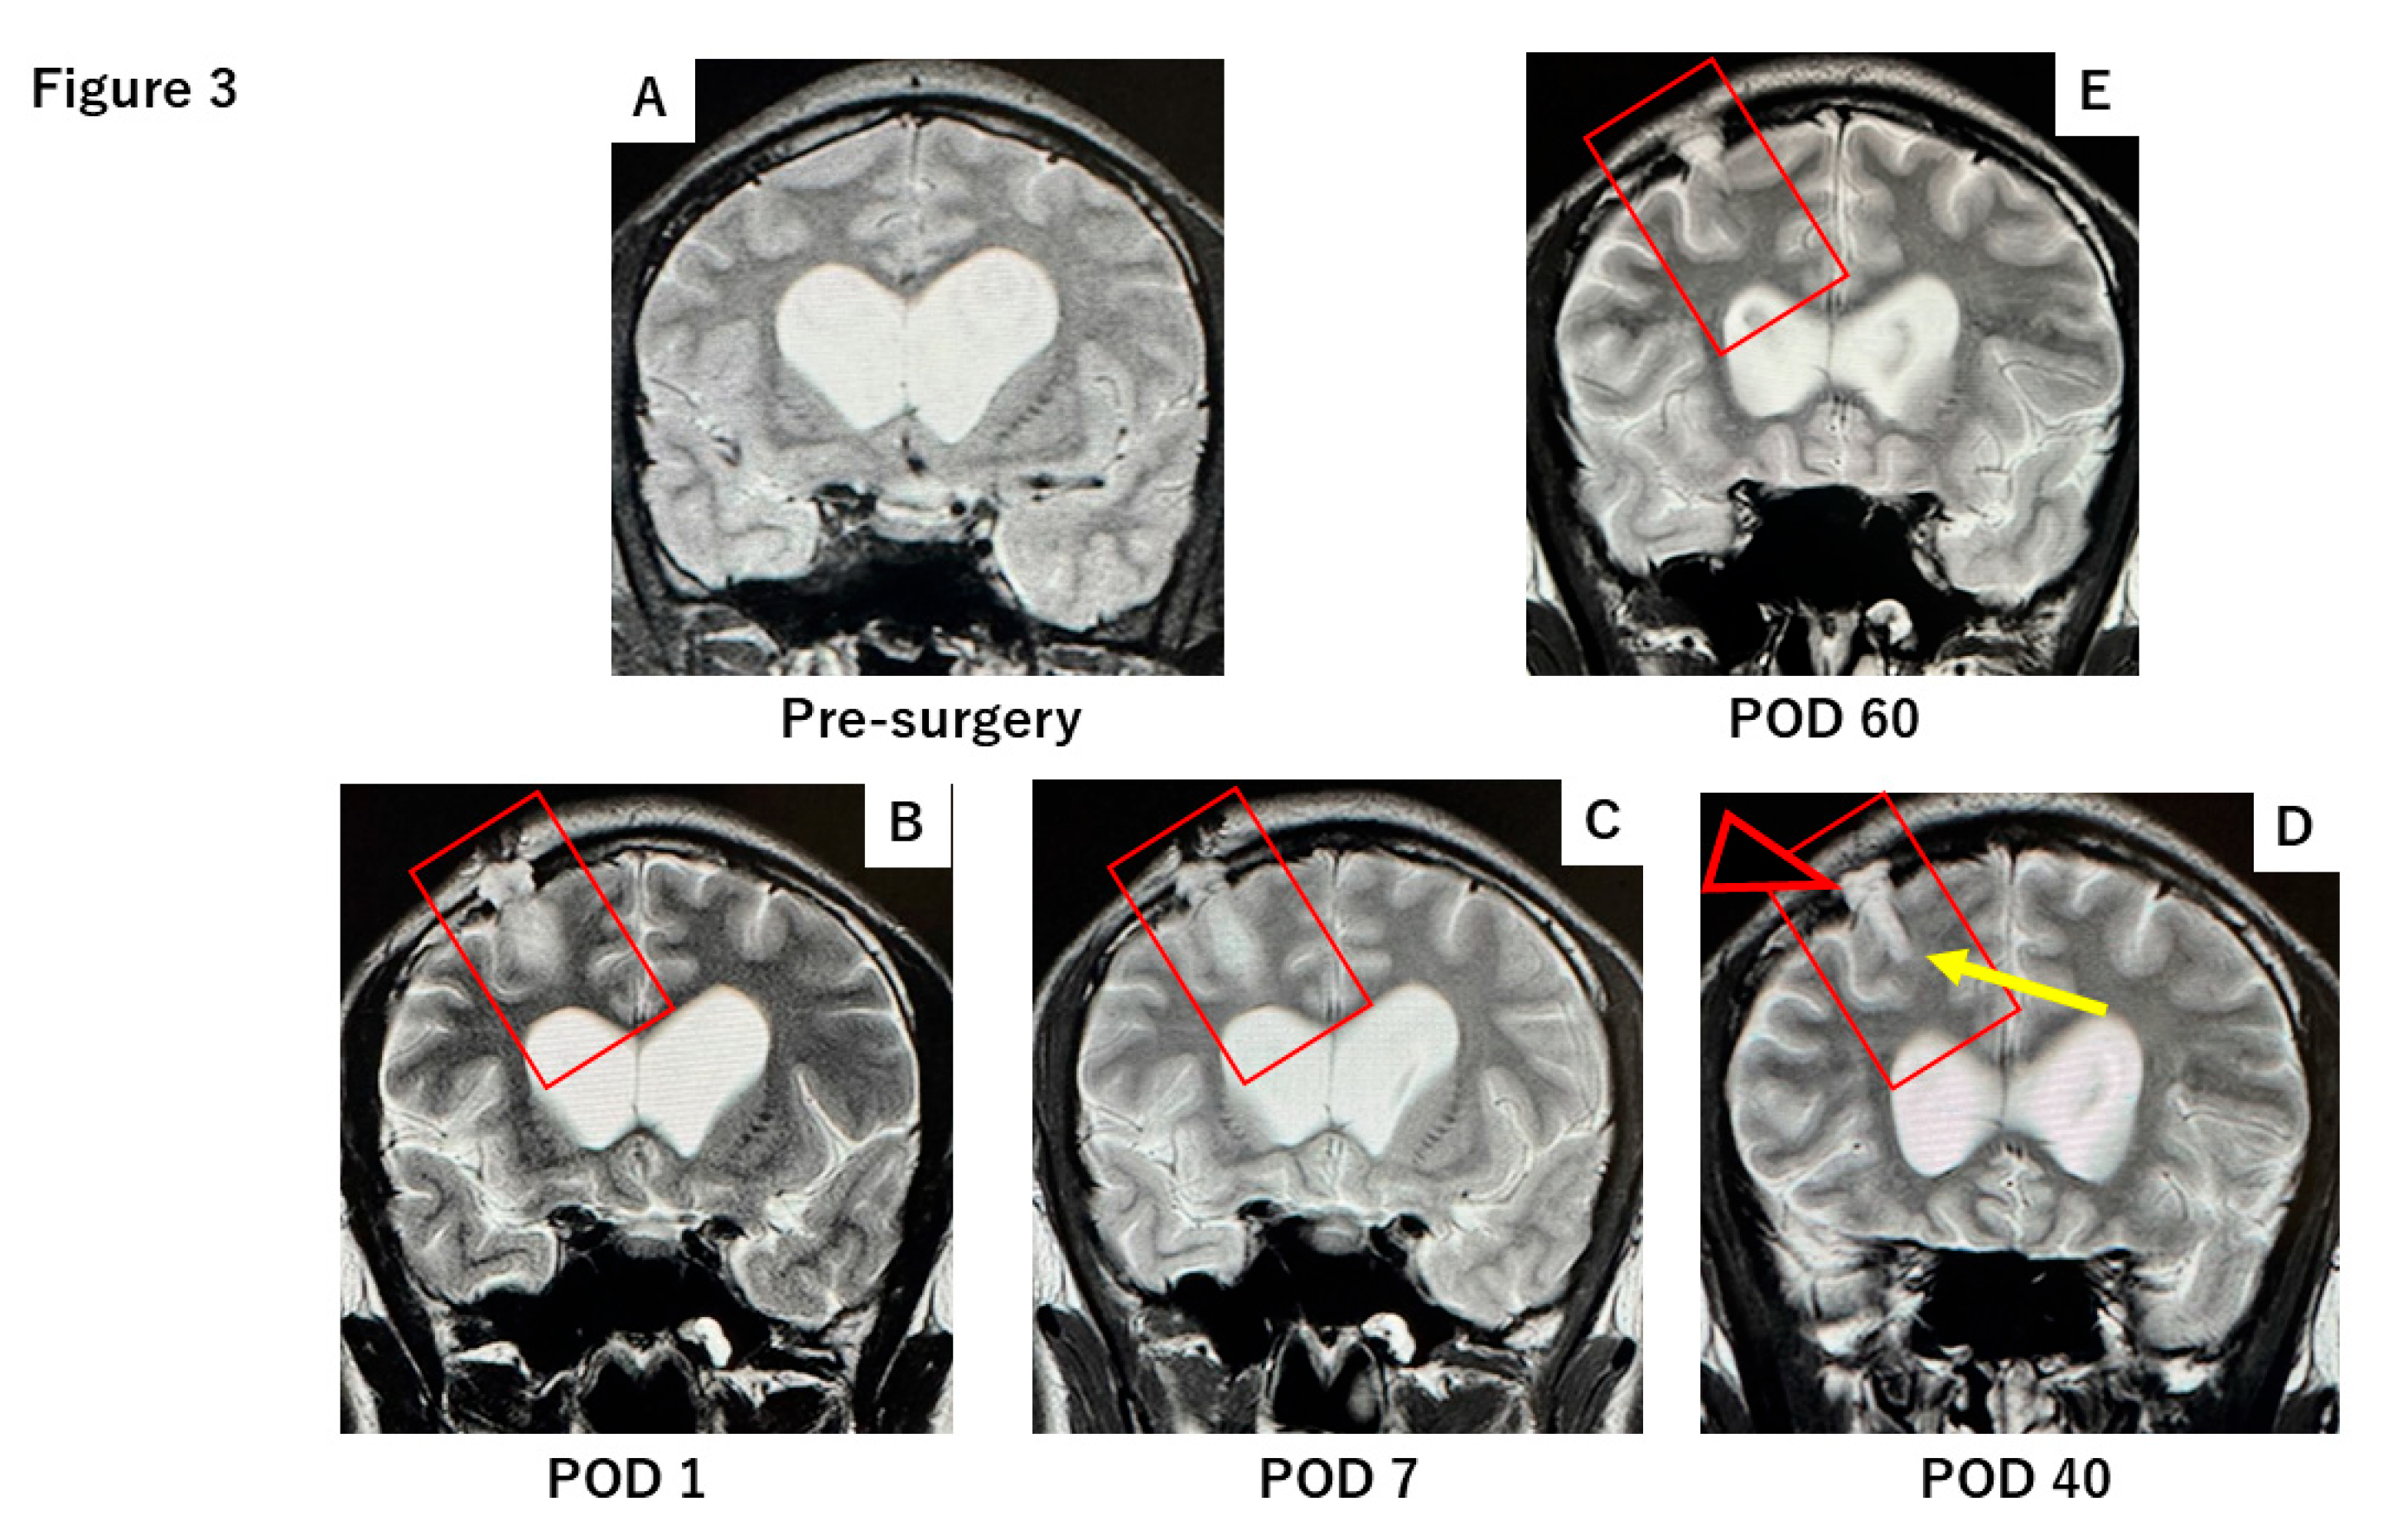

Follow-up MRI at postoperative 1, 7, 40, and 60 days demonstrated progressive resolution of the CSF leak, with the DuraGen matrix gradually absorbing and facilitating effective dural repair (Figure 3).

In contrast, the case using DuraGen showed no subdural or subcutaneous fluid effusion. The parenchymal defect gradually healed and was replaced by tissue of iso-intense signal to surrounding brain, with minimal granulation tissue. This regenerative process is evident in MR images at postoperative days 1, 7, 40, and 60 (Figure 3), which show the initial tract and faint high intensity along the pathway (day 1), partial absorption of CSF by day 7, and progressive parenchymal healing by days 40 and 60, along with dural restoration at the burr hole site.

Figure 3. T2-weighted MRI obtained at 1, 7, 40, and 60 days postoperatively following DuraGen insertion. After neuroendoscopic surgery via the NeuroPort sheath, DuraGen was inserted into the tract. (A) Pre-surgery MRI before DuraGen implantation. (B) A faint T2-hyperintense area is observed along the surgical pathway with the DuraGen implant on postoperative day 1 (POD1). (C) By POD7, the hyperintensity is reduced, indicating absorption of residual cerebrospinal fluid (CSF). (D) At one-month post-op (POD40), the tract that contained DuraGen shows evidence of regenerating brain tissue (white arrow). Additionally, new dural formation is apparent at the site of the dural onlay (black arrowhead), with no CSF leakage into subdural or subcutaneous compartments. € By POD60, the parenchymal tract has largely healed, appearing comparable to preoperative imaging.